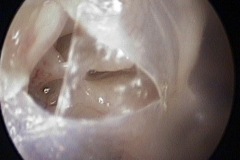

Perforation